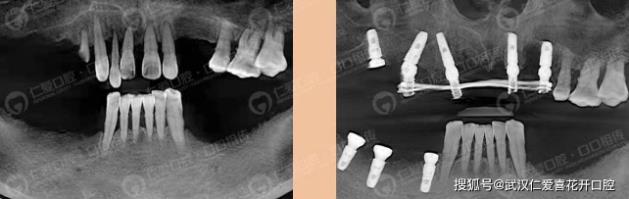

分享一則半口即刻負重種植案例:

患者特地從外地過來找席主任種植,當天拔牙,當天種牙,當天用牙,暢享口福!